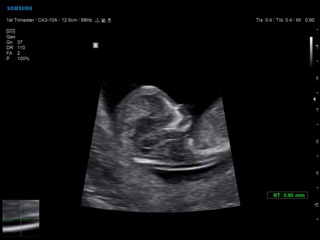

Atlas of ultrasound images - obsterics

In the section "Оbsterics" of atlas the results of ultrasonic examinations of pregnant women with different durations of gestation are represented. Here you can see images of internally organs, cerebrum, cordis and the sex of the fetus, the sonograms of multiple pregnancy, the blood flow in placenta and umbilical cord, defects of fetal`s development, etc.